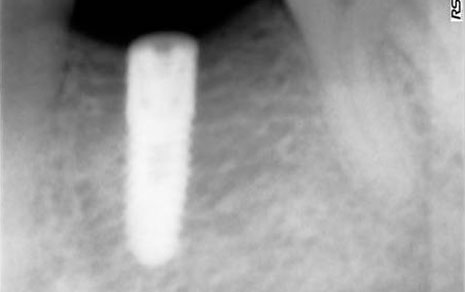

Single Tooth Implant

Replaces one missing tooth in a fixed and secure way.